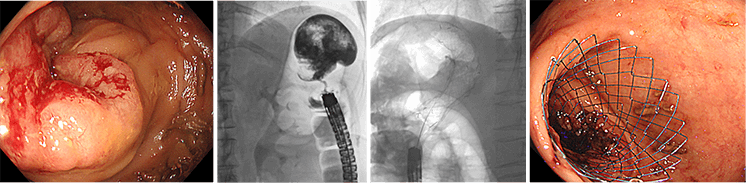

大腸が、がんなどで腸閉塞を来した場合に、金属製のステントを内視鏡で挿入し、通過を確保します。

下行結腸癌に対する緊急大腸ステント留置術